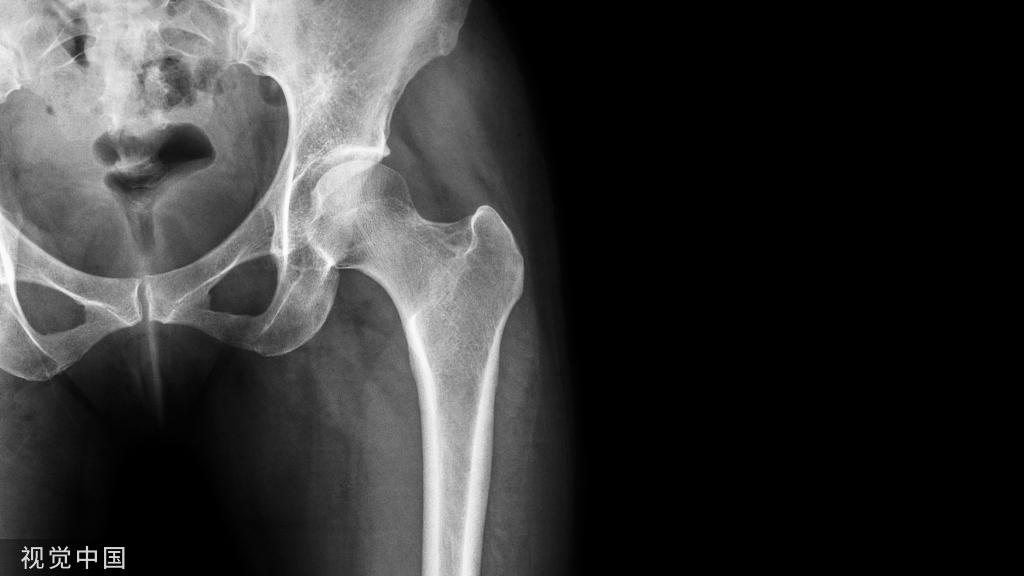

1)越早越好(6h之内,股骨颈骨折/髋关节脱位)。

2)48h之内(老年髋部骨折)。

3)髋臼骨折(伤后5-7天)

- 人体最大的负重关节,精确复位可达到关节的最佳匹配,确保正常力学性能;

- 影像学移位程度大,不匹配>2mm--手术;

- 髋关节脱位,髋臼后壁骨折并股骨头骨折,复位后关节仍然不稳,或关节腔有游离骨块--手术。

并发症:异位骨化18-90%;股骨头坏死3-9%

1)股骨近端(股骨头,颈,转子部位)

- <65岁,内固定;>65岁,关节置换。

- 患者全身情况稳定,应早期内固定。

- 内固定方式很多,如DHS,pfna等。